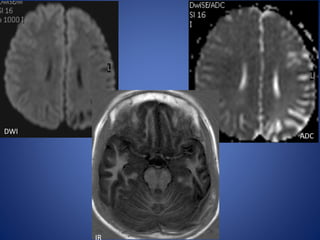

• 7 yr old girl, with sudden onset of severe right sided headache, followed

by left hemiparesis & slurred speech of one day duration.

• H/o Chickenpox 2 months back.

DWI

ADC

IR